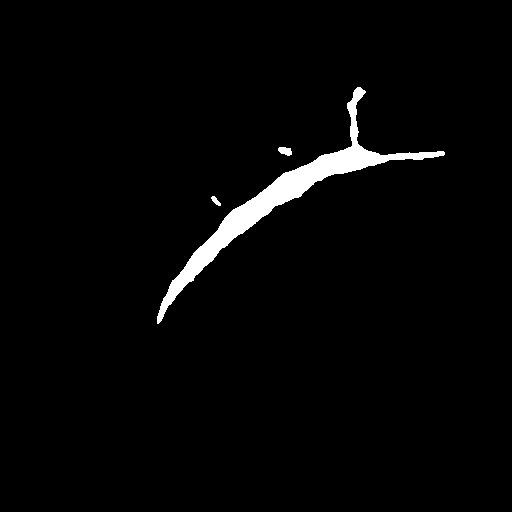

We evaluate the performance of each approach with five classical metrics: intersection over union (IoU), Dice score, precision, recall, and Hausdorff Distance (HD). We provide results on datasets , , and in Tables 1, 2, and 3, respectively. In Figure 2, we also illustrate representative segmentation results on dataset for each methods.

Raw

GT

U-net

CE-net

Attention U-net

AURA-net

The original U-net model produces poor segmentation results on datasets and while performing better on dataset . CE-net performs better than U-net and results in a strong recall in all three datasets. Attention U-net outperforms both CE-net and U-net on most metrics. The Attention gates incorporated in AURA-net allow outperforming CE-net, while its pre-trained layers help improve over Attention U-net. On top of that, the AC loss provides the network with additional information on object regions. As a result, AURA-net generally outperforms competing approaches. It occasionally scores closely to Attention U-net and CE-net, and even concedes a lead on recall in datasets and and on precision in dataset . It however performs best overall, with a consistent clear advantage on the IoU, Dice, and HD metrics.